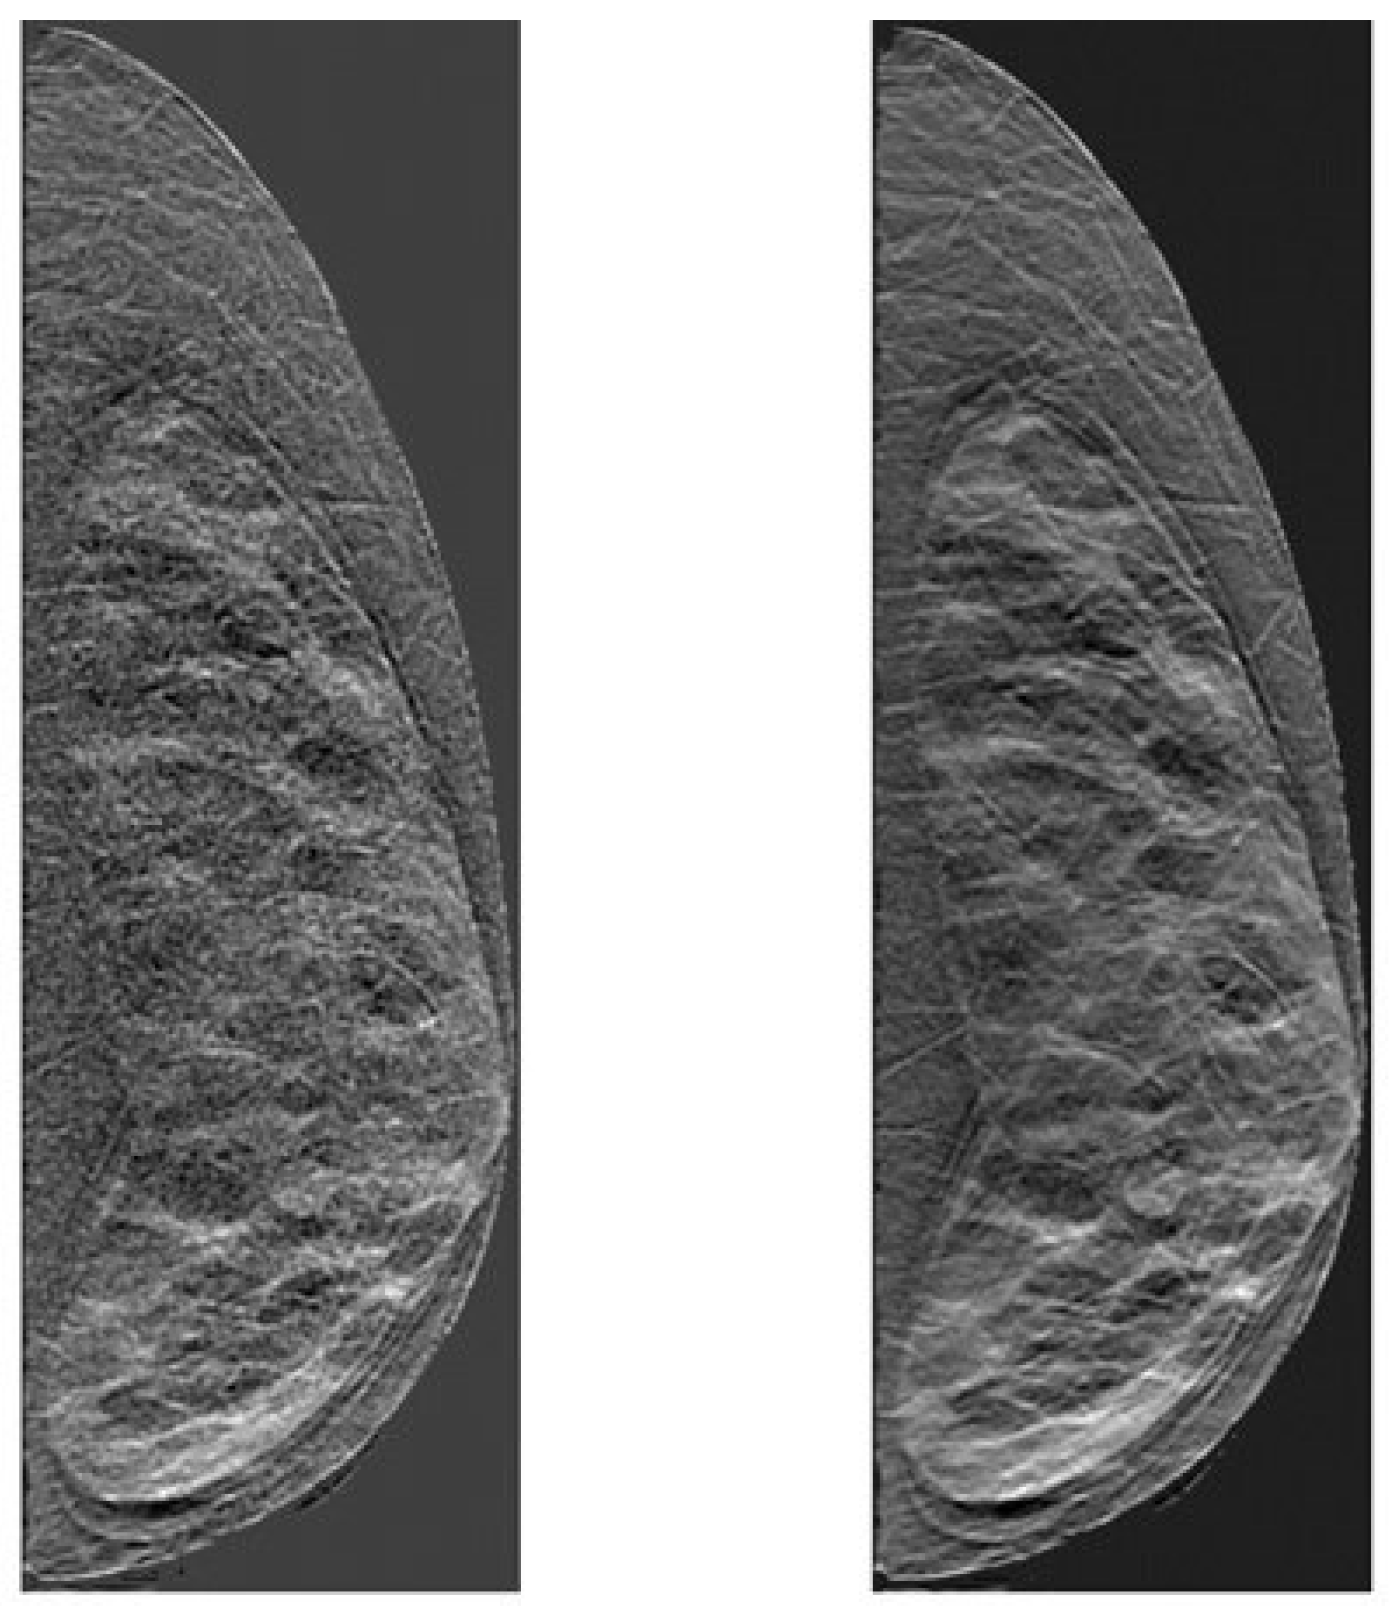

2.3. Clinical Data

- Kontos, D.; Ikejimba, L.C.; Bakic, P.R.; Troxel, A.B.; Conant, E.F.; Maidment, A.D. Analysis of parenchymal texture with digital breast tomosynthesis: Comparison with digital mammography and implications for cancer risk assessment. Radiology 2011, 261, 80–91. [Google Scholar] [CrossRef][Green Version]

- Kontos, D.; Bakic, P.R.; Carton, A.K.; Troxel, A.B.; Conant, E.F.; Maidment, A.D. Parenchymal texture analysis in digital breast tomosynthesis for breast cancer risk estimation: A preliminary study. Acad. Radiol. 2009, 16, 283–298. [Google Scholar] [CrossRef][Green Version]